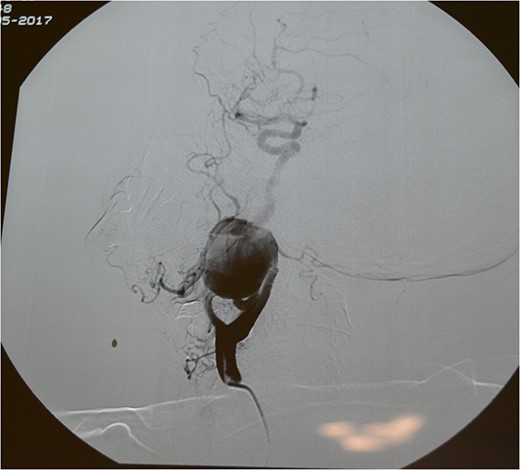

A 71-year-old woman was referred to the vascular surgery department of our hospital with an asymptomatic, pulsative, submandibular mass that she had noticed in the right side of her neck for a month and with ‘potato voice’. Her medical history was non-contributory. MRI, 3D-CT (Fig. 1) and conventional angiography (Fig. 2) revealed an aneurysm of the right ICA. The aneurysm was located in the upper third of the artery and its maximal diameter was more than 4 cm, lining to the right parapharyngeal space, whereas the aerodigestive track was limited and dislocated in the height of the aneurysm.

Operatively, after induction to general anaesthesia via orotracheal intubation, an extended submandibular incision to the right of the neck was performed and the mandible was revealed. The marginal branch of the facial nerve was recognized and protected. Following this, the double osteotomy of the mandible was performed in the parasymphysis—with preplating of two miniplates with four holes—and in the subcondylar area—with preplating of two miniplates with four holes (Figs 3 and 4). The mandibular ‘swing’ that was performed straight after that (Fig. 5) gave space for the dissection of the CCA and the bifurcation. All the branches were prepared, and the aneurysm was accessed (Fig. 6). The reconstruction was achieved by bypassing the aneurysm, trans-positioning of the right ECA and end-to-end anastomosis of the ECA with the healthy peripheral end of the ICA near the skull base, after the lignification of the peripheral end of the ECA and its smaller branches (Fig. 7). The anastomoses were checked for leakage (Fig. 8), the mandible was reduced and the easily fixated rigidly after preplating (Fig. 9).